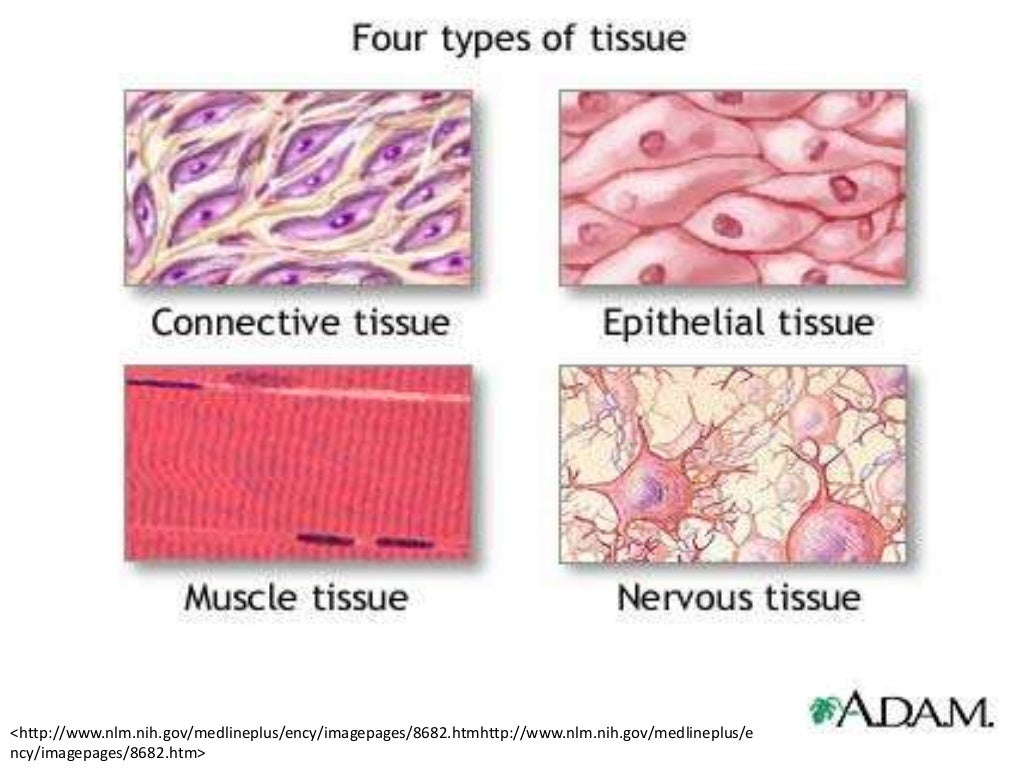

Soft Tissue Diagram

Soft Tissue Diagram

The 4 Types Of Tissue